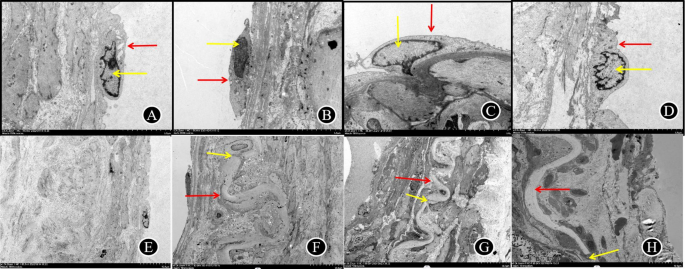

Ultrastructural observations: (Table 6, Figs. 3 and 4)

Typical picture of TEM results of hemorrhagic MMD(D-F is local magnification of A-C). A (X1000 times) The internal elastic lamina is discontinuous and local residual, more smooth muscle cells migrating to the inner membrane layer. Endothelial cells were mostly shed and free, exhibiting damaged cell membranes, irregular nuclei, without obvious mitochondrial swelling, and with rough endoplasmic reticulum expansion. The basement membrane was sparse and notably thickened. B (X3000 times) Smooth muscle cells are neatly arranged with slightly enlarged intercellular gaps. The cells exhibit relatively regular nuclear morphology, clear and intact nuclear membranes with defined heterochromatin, few organelles, uniform mitochondrial matrix, thick endoplasmic reticulum showing membrane dissolution, and abundance. The local dense spot is significantly longer, and the number of dense bodies is more abundant. C (X3000 times) Fibroblasts are disintegrated, necrotic, and fragmented with disappeared cell membranes. There are abundant collagen filaments around the cells, irregular nuclei, fixed contraction, increased heterochromatin, uneven chromatin, and disappearance of other organelle structures. IEL: internal elastic lamina; BM: basement membranae;Enc: endothelial cells; N: nucleus; M: mitochondria: RER: rough endoplasmic reticulum; SMC: smooth muscle cell; DP:dense patches; DB: dense body;Fb:Fibroblasts; CF: collagen filament.

Typical picture of TEM results of ischemic MMD(D-F is local magnification of A-C). A (X1000 times) The internal elastic lamina has uneven thickness, local rupture, and massive migration of smooth muscle cells to the intimal layer more smooth muscle cells migrating to the inner membrane layer(red arrow). Endothelial cells have mild hyperplasia, with fair cell matrix, irregular nucleus and slightly swollen mitochondria, shallow matrix and slightly broken crest, and slight expansion of rough endoplasmic reticulum. The basement membrane is locally sparse and mildly thickened. B (X3000 times) Smooth muscle cells are long spindle shape, mild swollen, large, regular arrangement and fair intercellular spaces. The nucleus is spindle shaped, not widened, heterochromatin increases and edge set; mitochondria is relatively abundant, mostly swollen, uneven matrix, broken, shorter and reduced, and a few membranes are damaged; rough endoplasmic reticulum is expanded and membrane is damaged; dense spot is significantly longer and increased, and the number of dense body is small and evenly distributed. C (X3000 times) Fibroblasts are disintegrated, necrotic, and fragmented with disappeared cell membranes. There are abundant collagen filaments around the cells, irregular nuclei, fixed contraction, increased heterochromatin, uneven chromatin, and disappearance of other organelle structures. IEL: internal elastic lamina; BM: basement membranae;Enc: endothelial cells; N: nucleus; M: mitochondria: RER: rough endoplasmic reticulum; SMC: smooth muscle cell; DP:dense patches; DB: dense body;Fb:Fibroblasts; CF: collagen filament.

Intima the majority of vascular endothelial cells of hemorrhagic MMD patients showed necrosis and detachment, while the IEL appears wavy, thin, and ruptured. Many smooth muscle cells were seen in the intimal layer, while endothelial cell nuclei exhibit irregular morphology, heterochromatin borders, variable mitochondria, and dilated endoplasmic reticulum.

In ischemic MMD, vascular endothelial cells exhibit varying degrees of edema, necrosis, and shedding similar to hemorrhagic MMD. The IEL shows waviness, visible thinning, and discontinuity. Smooth muscle cells abundantly migrate to the intimal layer. Irregular nuclear morphology with a heterochromatin border is noted, along with varying numbers of mitochondria and dilated endoplasmic reticulum.

Media In hemorrhagic and ischemic moyamoya disease, abundant smooth muscle cells are observable on the surface of cerebral blood vessels. The majority of the nuclei displayed an elongated spindle shape, while the density of both DP and DB within the plaques varies.

Adventitia In hemorrhagic and ischemic moyamoya disease, there is significant fibroblast disintegration, scattered organelles, and abundant collagen fibers surrounding the cells.

The score of IEL rupture in hemorrhagic ([M(Q1, Q3) = 2 (1,3)]) and ischemic MMD [M(Q1, Q3) = 1 (0,2)]), showed a statistically significant difference (P = 0.013), suggesting a notably higher incidence of internal elastic lamina injury in patients with hemorrhagic presentation (Table 7, Figs. 3 and 4).

The area of vascular endothelial cells were statistically difference in hemorrhagic MMD ([M(Q1,Q3) = 12.68 (1.08,20.90) μm2]) ([M(Q1,Q3) = 16.42 (10.20,23.36) μm2]) (P = 0.046). Endothelial cells in hemorrhagic MMD showed significant contraction compared to those in ischemic MMD (Table 7, Figs. 3 and 4).